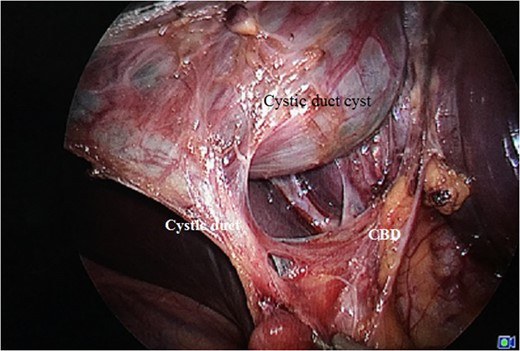

Laparoscopic view showing Calot's triangle dissected with choledochal cyst seen separately from the rest of the GB.

The management of Type VI choledochal cyst is guided by its morphology [1–7]. The surgery recommended for Type VI choledochal cyst with a narrow-based cystic duct stalk is simple cholecystectomy with cyst excision. Wide-based cystic duct with proximity to the CBD warrants a CBD excision along with the above procedure and bilio-enteric reconstruction. Most of the authors reported in the literature have described the surgery by open or laparoscopic converted to open route. We did a complete laparoscopic mobilisation and cyst excision with cholecystectomy in the present case. Detailed assessment of the histology is important to detect any neoplastic changes. In patients undergoing CBD excision as a part of the procedure, evaluation of the margins for neoplasia is important. Proved malignancy of the cyst with CBD or GB warrants a definitive procedure in the form of Whipple's operation or radical cholecystectomy, respectively.